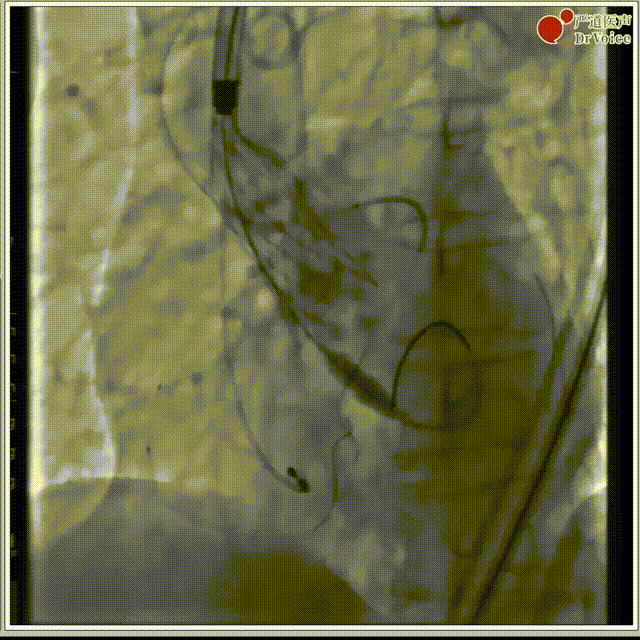

7. 复查造影,左冠有遮挡风险,遂行“烟囱支架”。

释放后左冠造影

支架释放后造影

8. 右冠显影正常,无遮挡风险,撤离导丝。

右冠造影

9. 术后超声评估。

最后瓣膜植入情况

术后超声